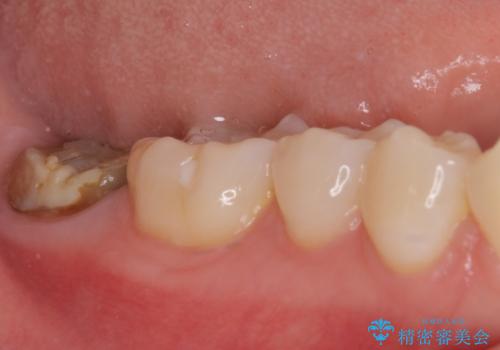

歯の高さが低く、かぶせものを安定して維持させることができないため、歯冠長延長術により歯の高さを増大させた上で、オールセラミッククラウンにて補綴することとしました。

クラウンが外れている期間も長く、虫歯が進行していたため、根管治療も行うこととしました。